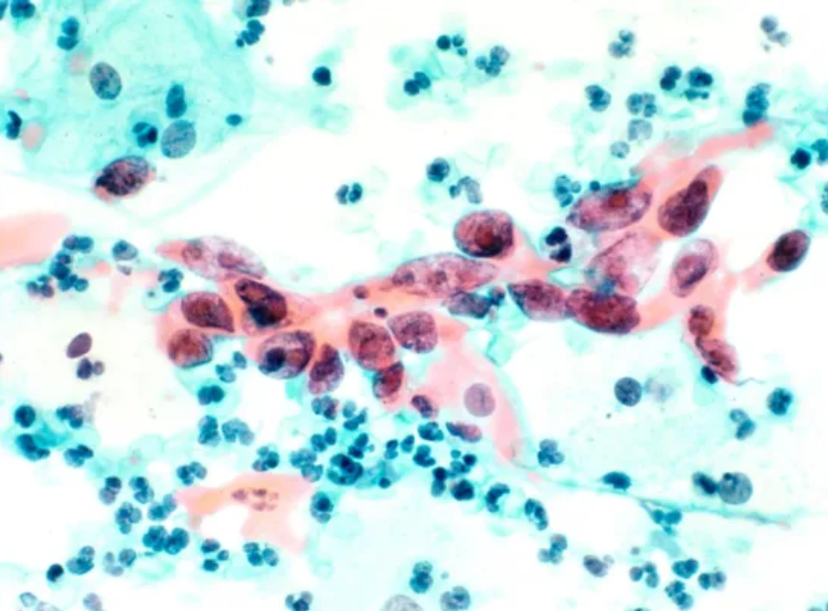

A magnified image of squamous cell carcinoma, the most common type of cervical cancer.